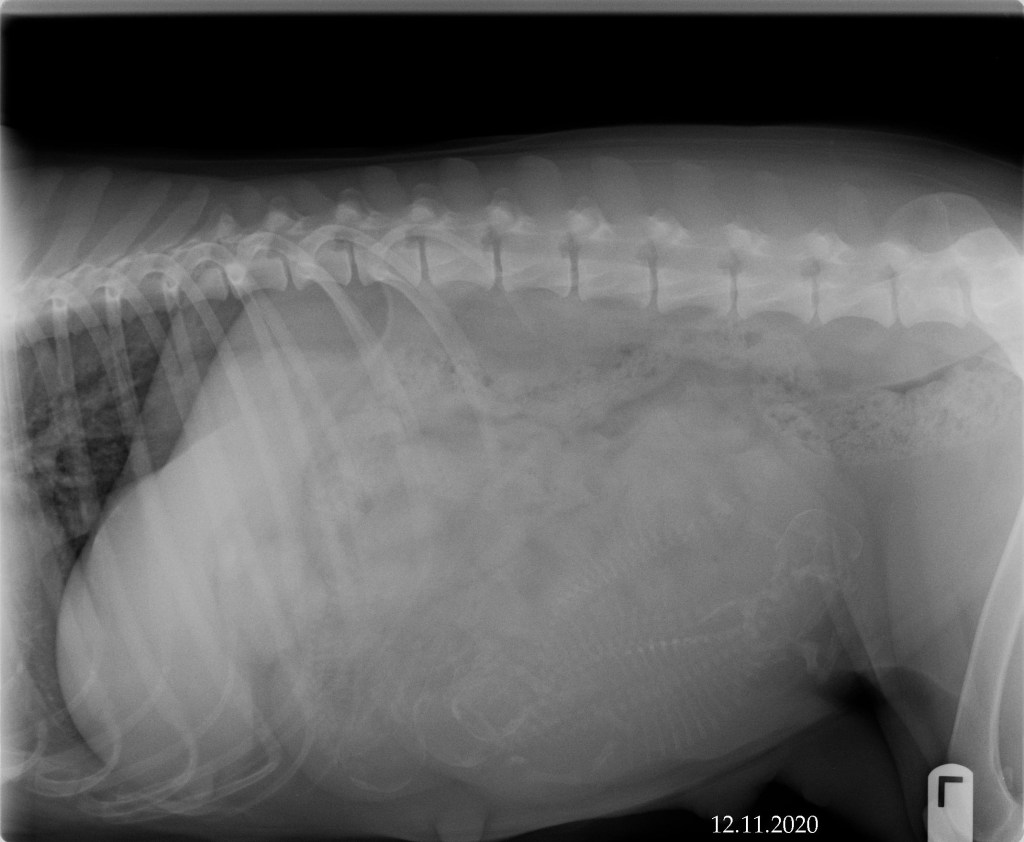

December 11, 2020 – X-ray

Today is always one of my favorite days of pregnancy. Kimber’s abdomen was x-rayed so that we could get a general count of how many puppies we should expect. Dr. Harr is usually right on when she counts the little skeletons. She says that we should anticipate 4 puppies! Although it is a smaller litter, we are very excited to welcome them into the world sometime next week!